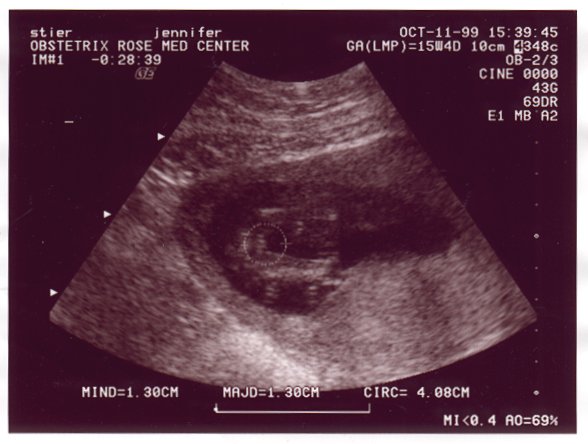

Ultrasound Picture No. 1